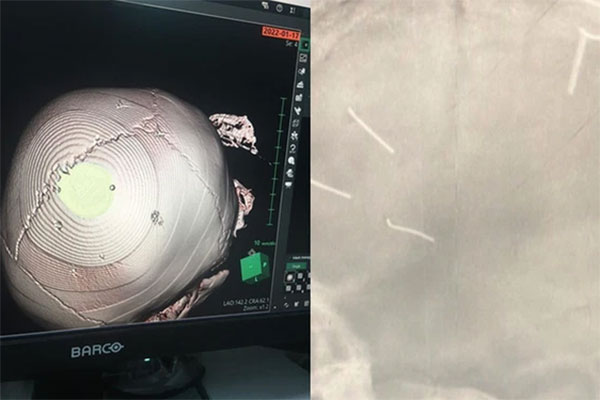

Sau khi chụp X-quang, các bác sĩ giật mình phát hiện trên sọ cháu bé có những vật thể giống kim khí găm bên trong, tổng cộng 9 chiếc trong sọ não cháu bé.

Thời điểm cháu bé nhập viện có mẹ cháu đi cùng, trên đầu có chút sưng tấy. Khoảng 1 tiếng sau khi cấp cứu, bệnh nhi được chuyển lên Bệnh viện Đa khoa Xanh Pôn.